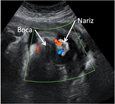

Ecografía 4D del tercer trimestre: Feto de 24 semanas

Esta ecografía 4D de la cara de un bebé muestra claramente los gestos de la criatura. Con sólo de 24 semanas de edad gestacional, se ve cómo el pequeño traga líquido amniótico. Además, abre y cierra una de sus manos.

Ecografía 4D de un feto de 24 semanas haciendo gestos con la cara

Aunque en esta ecografía en 4D la fisonomía de bebé no se ve muy clara, lo que se aprecia perfectamente es la gesticulación de la cara y de una extremidad superior de la criatura. El feto, con una edad gestacional de 24 semanas, traga líquido amniótico y abre y cierra una de sus manos.